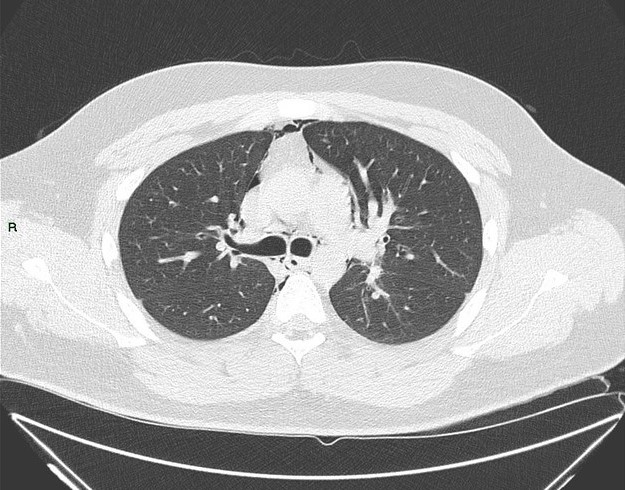

Tràn khí trung thất

Tràn khí trung thất - Ảnh 3

» Thông tin: Nam giới – 25 tuổi.

» Lâm sàng: Đau ngực.